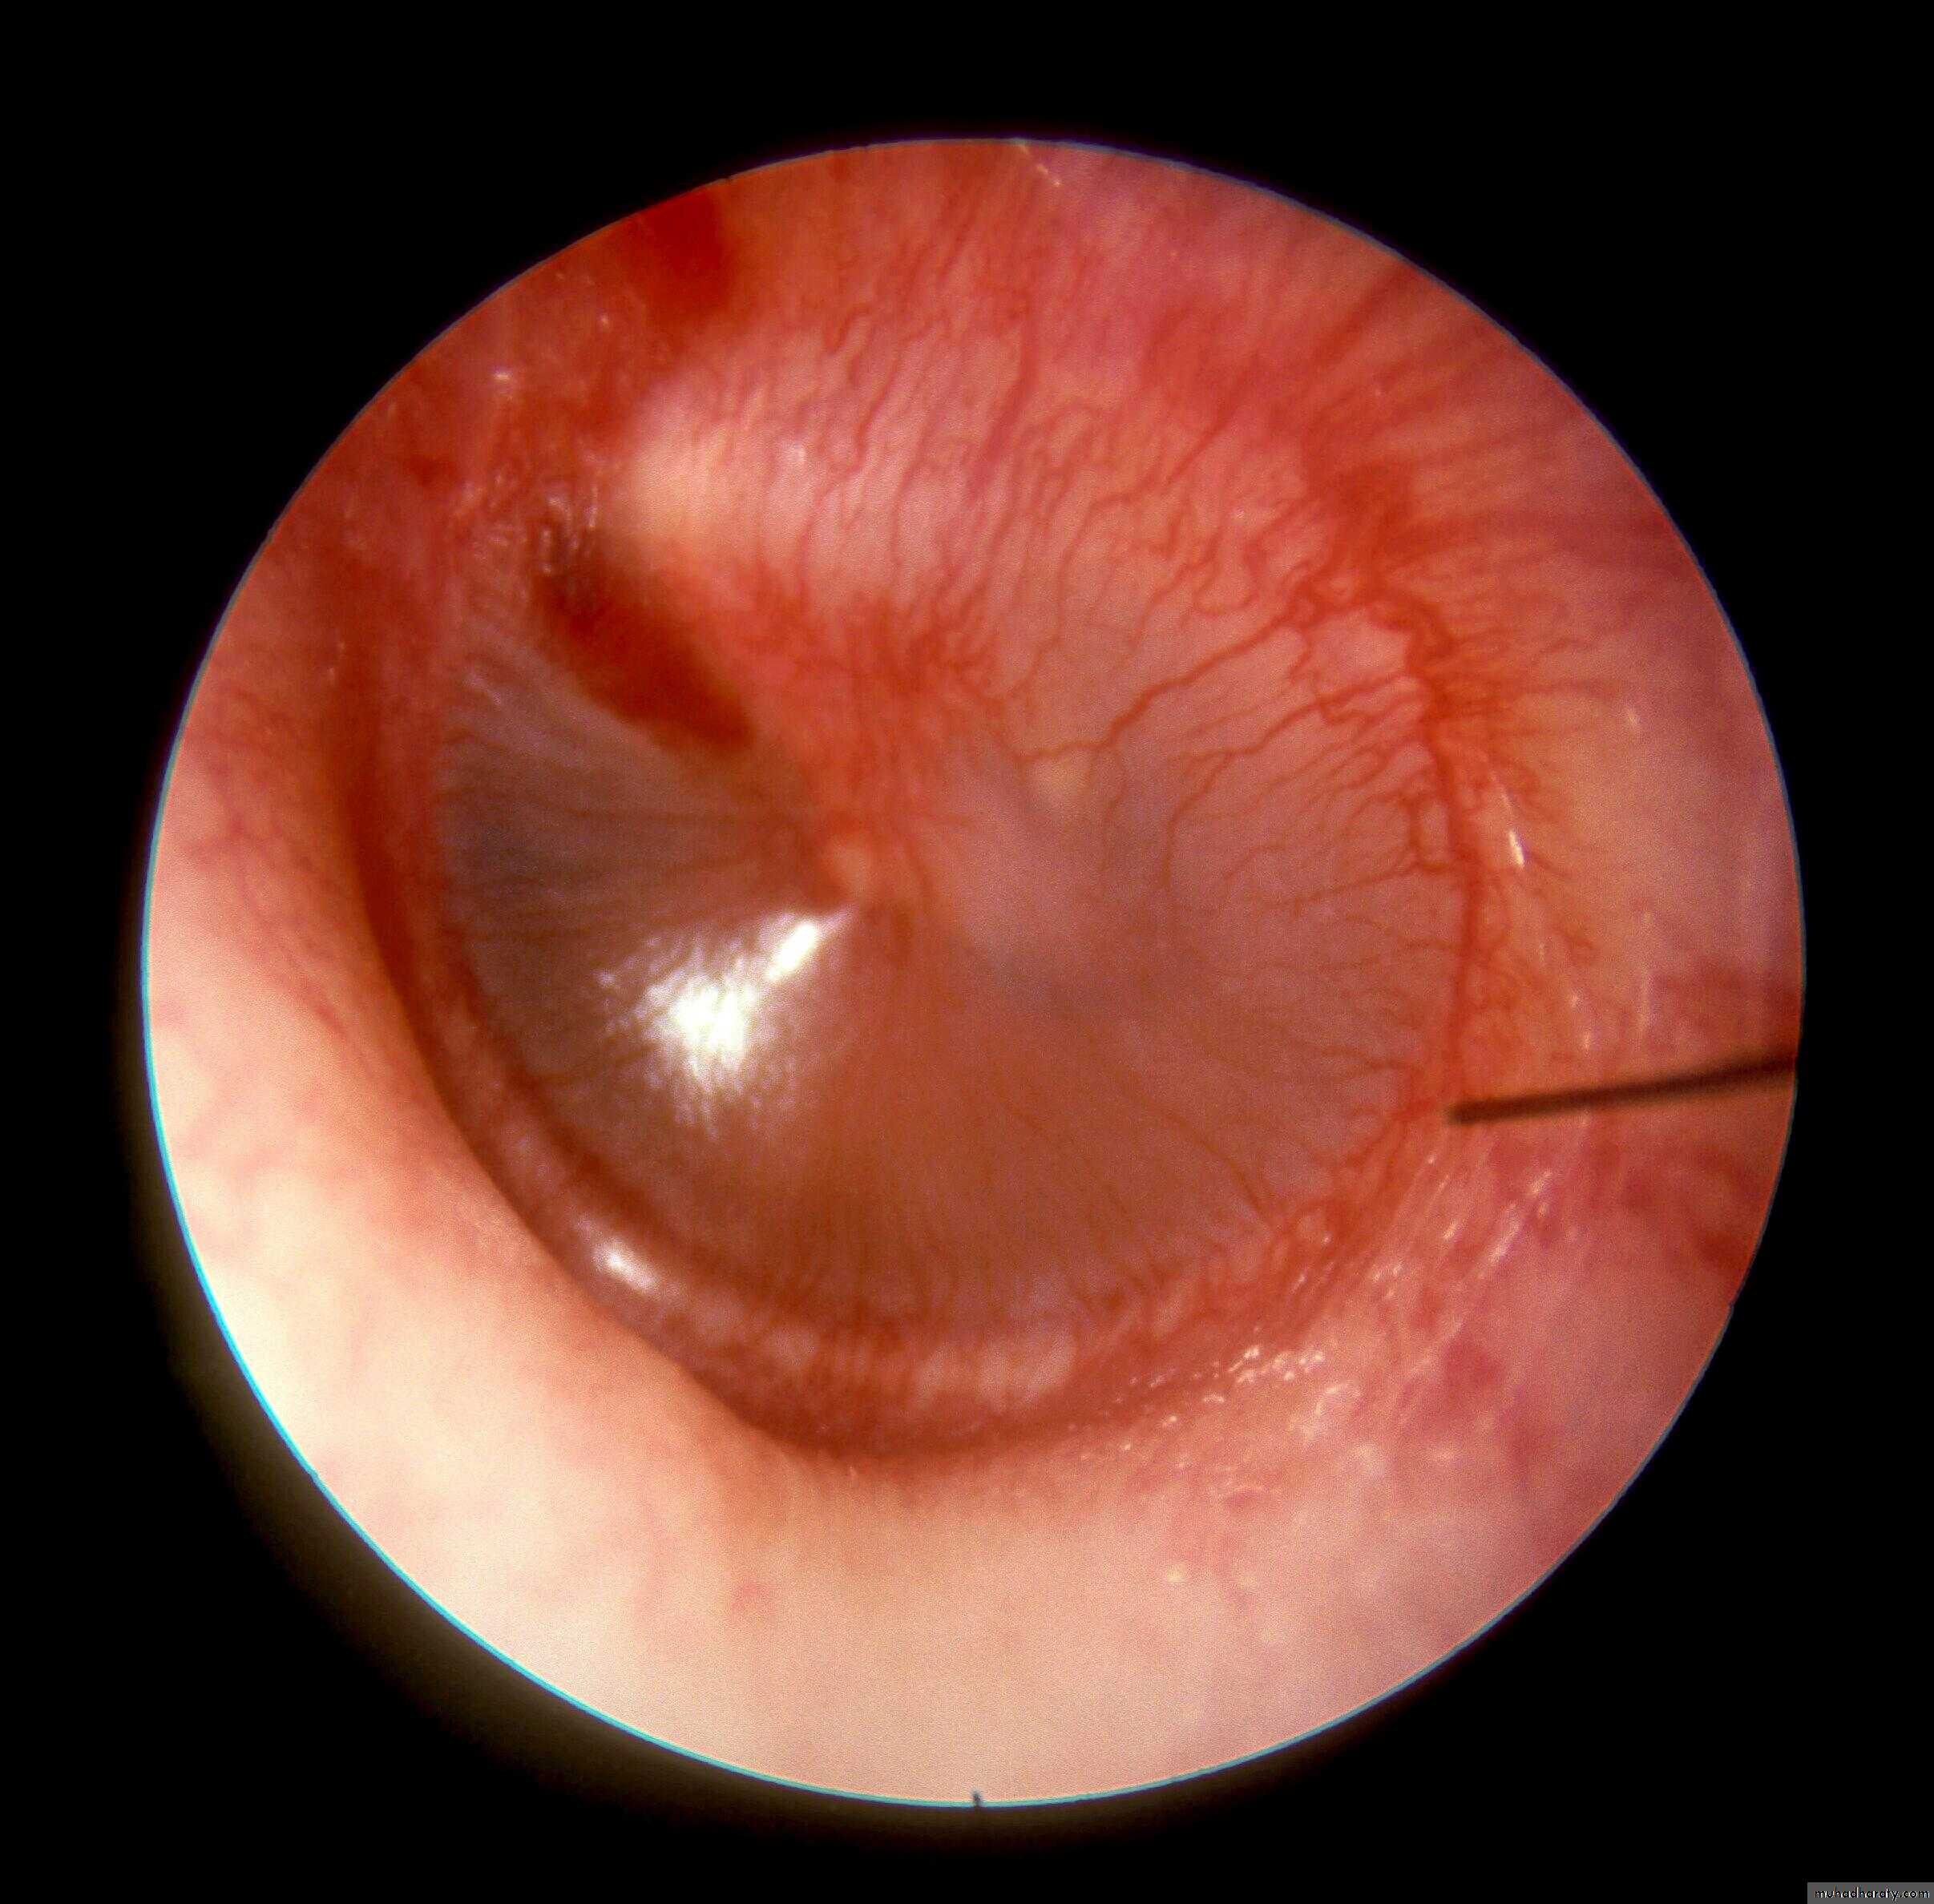

Dull and retracted TM

Handle of the malleus is prominent, foreshortened and more horizontal. Slide 16

The color of the TM is pale yellow, sometime grey or even blue.

Sometime fluid level (hair line) or air bubbles are seen. The fluid is usually clear, yellow, serous and sterile (no bacteria or inactive bacteria).